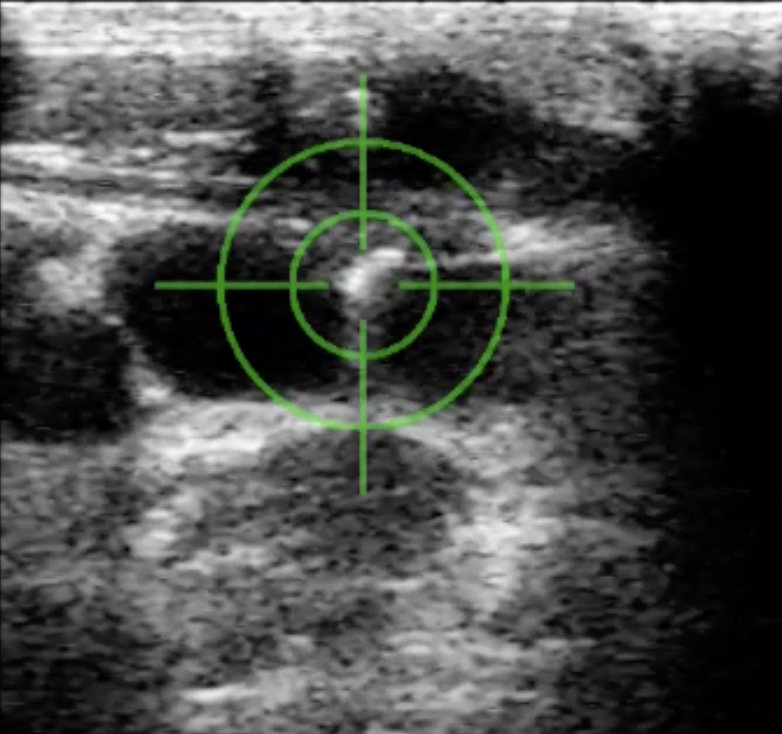

Vessel targeting with CERTA™

In May 2023, OBVIUS Robotics completed its initial clinical cases with the CERTA™ handheld device. Users were able to quickly visualize the target vessel and advance a needle in seconds to the target location. This was done with 100% access success

across both experienced and inexperienced users.